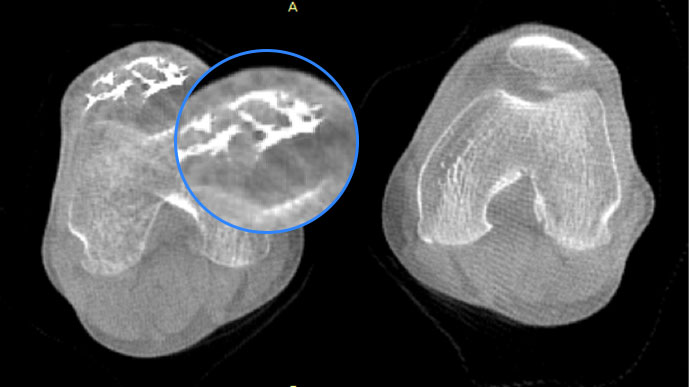

膝关节